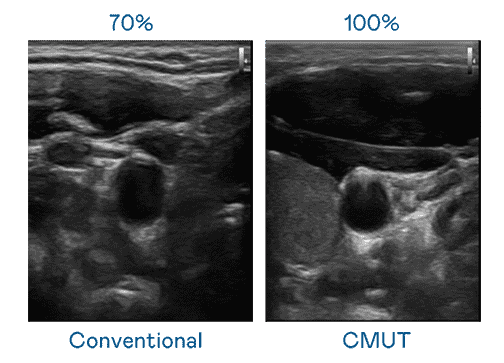

CMUT 技术是一种用电容式微机电元件来产生超音波讯号的技术。。与传统 PZT 压电式技术相比,,CMUT 频宽增加 30%,,更宽频的超音波讯号让影像解析度大幅提升,,,是实现高影像品质医疗超音波扫描、、、促进精准医疗发展的关键技术。。。

超音波影像的解析度高低,,首先取决于探头能发出的讯号频宽。。彩神vll CMUT 可提供高清晰的超音波讯号,,,,提供高频宽、、、、高灵敏度、、影像纹理细节更高的超音波影像,,,协助医护人员缩短影像判读时间及利用精准的医疗影像进行诊断。。。